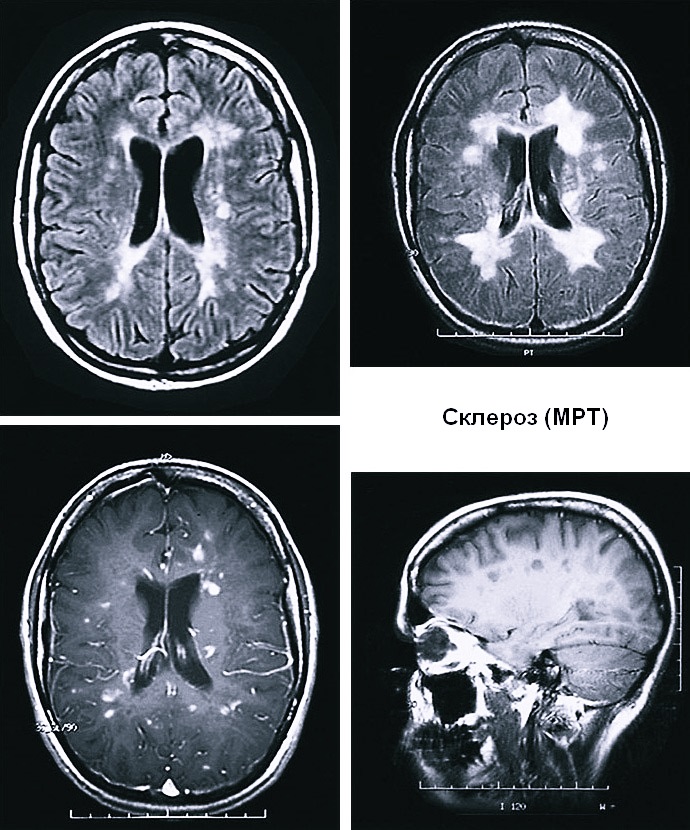

Практически во всех случаях многоочаговые поражения можно подтвердить с помощью магнитно-резонансной томографии (МРТ). Она позволяет диагностировать очаговые повышения интенсивности сигналов в головном или спинном мозге на полученных в специальном режиме изображениях. Порой, при наличии запущенного хронического процесса, возможно слияние очагов патологии и формирование из них зон с гиперинтенсивным сигналом. При этом выявляют вторичную атрофию мозгового вещества.

Особо эффективна магнитно-резонансная томография с использованием контрастных препаратов. С этой целью широко используется Магневист и препараты на основе гадолиния. Они позволяют усилить сигналы от воспалительных очагов, что помогает определять «молодые» участки повышения проницаемости гемато-энцефалического барьера. Таким образом, можно отслеживать активность патологических процессов.